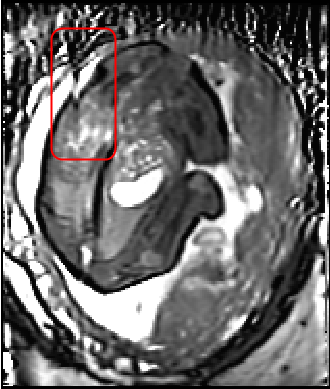

Fig. 3 shows a similar comparison for abdominal MRI of a pregnant patient. As highlighted in the red box, where the artifact is caused by a deep breath, due to lack of a good target with only one stack of 2D MR images, the state-of-art SVR method failed in the area with large motion corruption.